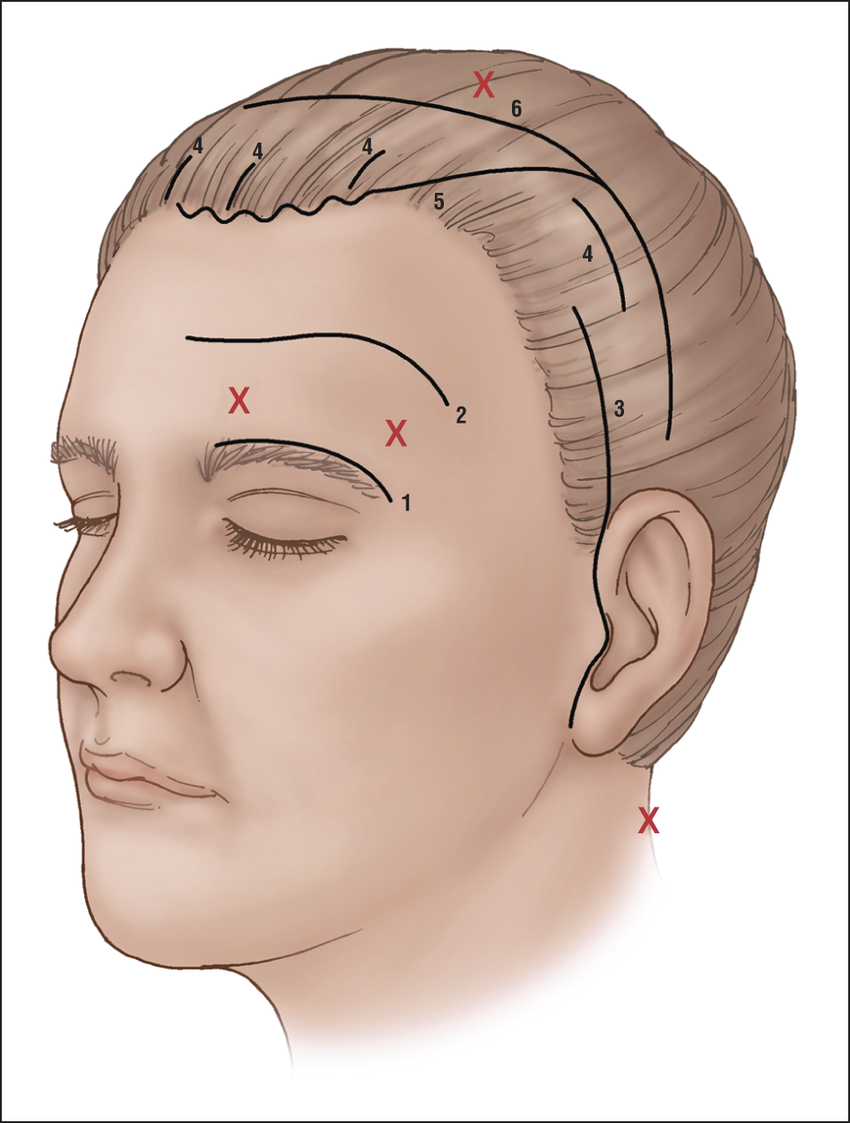

Value added benefits of the Minimally Invasive Surgery with Carotid Endarterectomy: